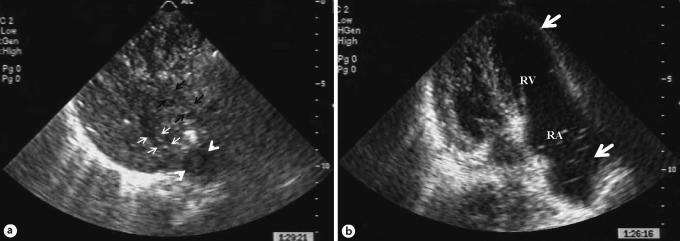

We describe a case of pulmonary gas embolism caused by portal vein gas (PVG) observed using echocardiography. Echography revealed gas flowing through the hepatic vein, inferior vena cava, right atrium, and right ventricle, as well as pulmonary hypertension. The patient was diagnosed as having pulmonary gas embolism caused by PVG.

我们描述了一例通过超声心动图观察到的由门静脉气体(PVG)引起的肺气体栓塞病例。超声检查显示气体流经肝静脉、下腔静脉、右心房和右心室,同时伴有肺动脉高压。该患者被诊断为由PVG引起的肺气体栓塞。

由PVG引起的气体栓塞死亡率为67%,6例血培养呈阳性,3例出现肺水肿。PVG最初会激发微泡形成,导致肝脏组织损伤和肝脓肿。大量的PVG会导致门静脉阻塞。结果,可能会发生门静脉高压、门体分流或胃肠道充血。PVG可通过肝脏或门体分流无异常地进入体循环静脉,引起肺气体栓塞,随后导致动脉栓塞。在这种情况下,败血症很容易发生。超声心动图对诊断由PVG引起的气体栓塞很有用,但气体可能会间歇性出现。肺水肿的表现对由PVG引起的肺气体栓塞很重要。